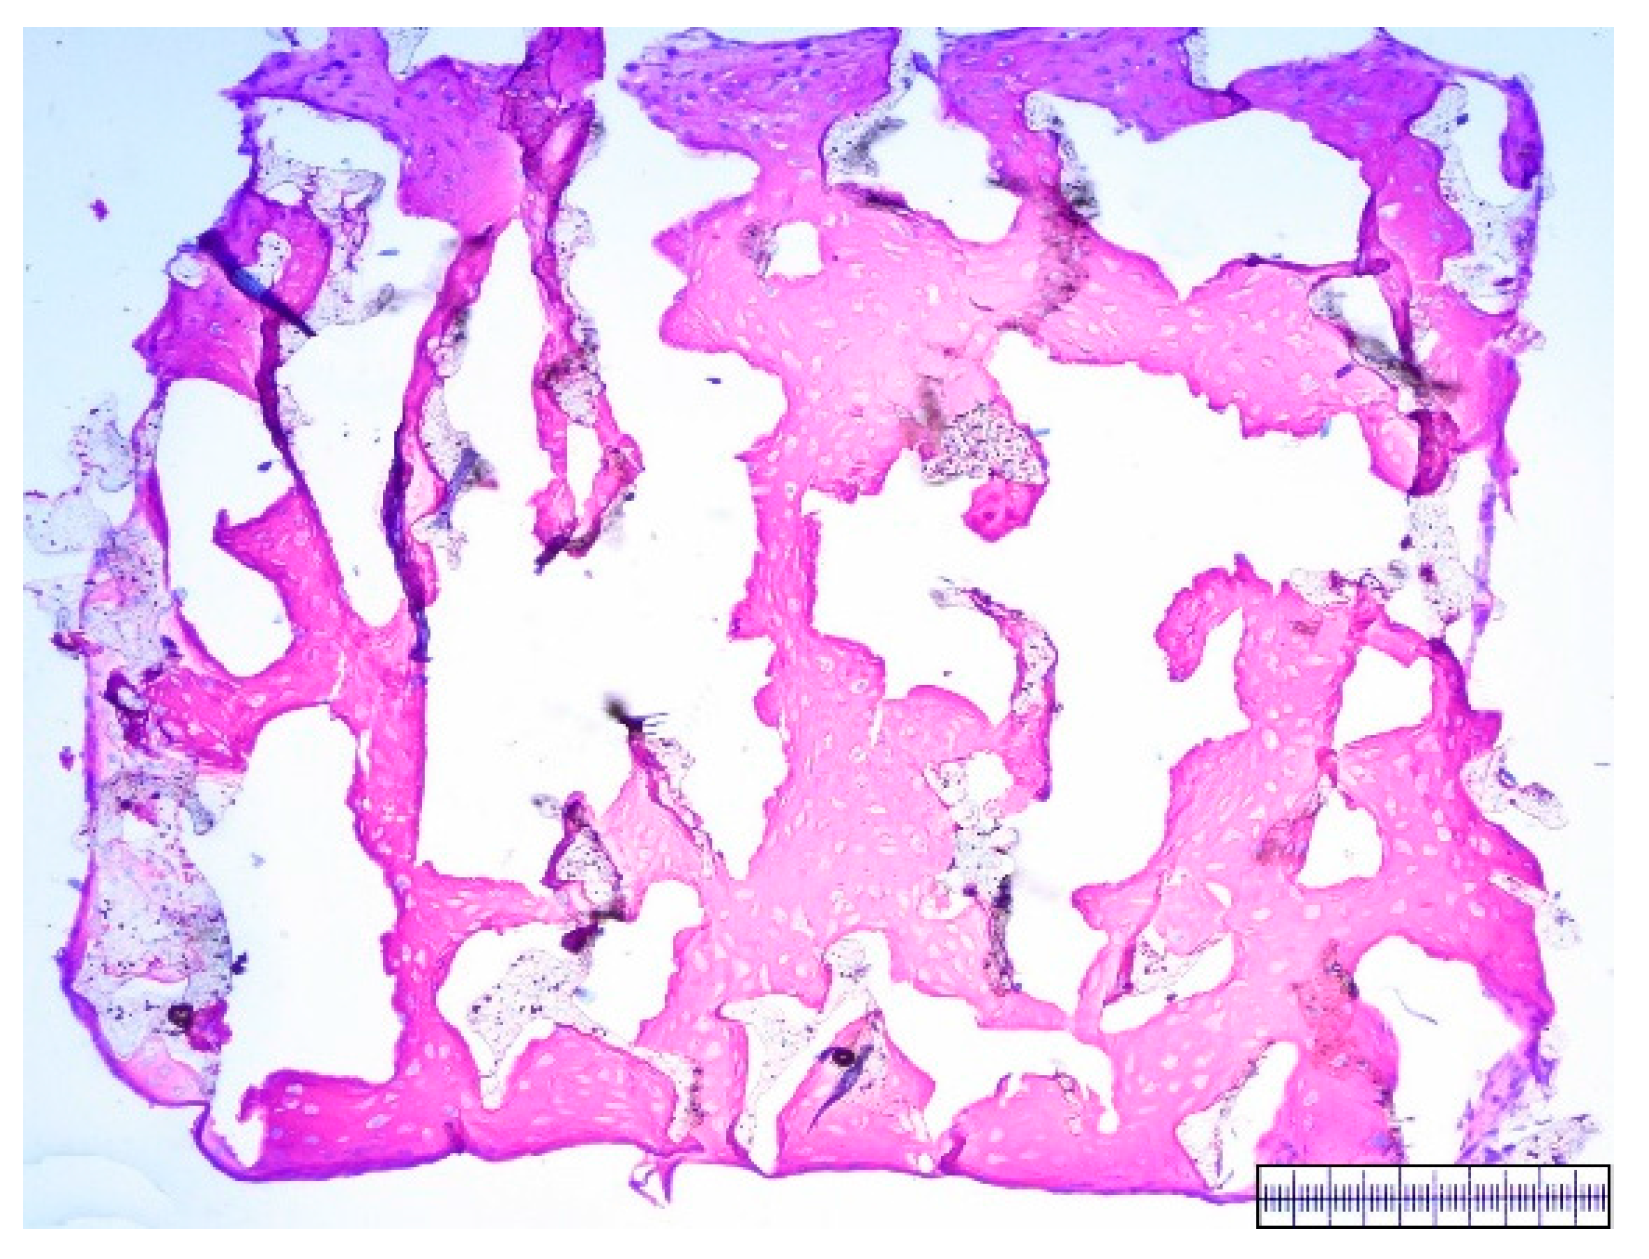

3.1. Macroscopical Assessment of Scaffold Pore Structure

3.2. Interconnectivity of Scaffold Pores